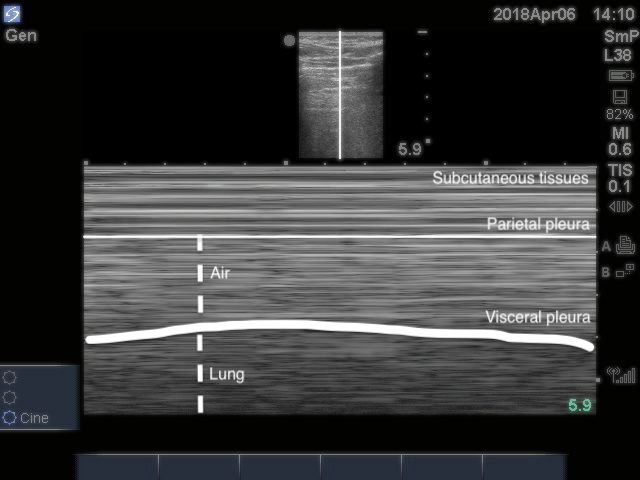

Lung Sliding

- Horizontal to-and-fro sliding movements of the visceral pleura in synchrony with respiration along the directly apposed parietal pleura, as seen in B-mode

- Can also be visualized in M-mode (Image 8) and using power Doppler61 (Video 4)

- Figure 8. Seashore sign

- Lung sliding rules out PTX16